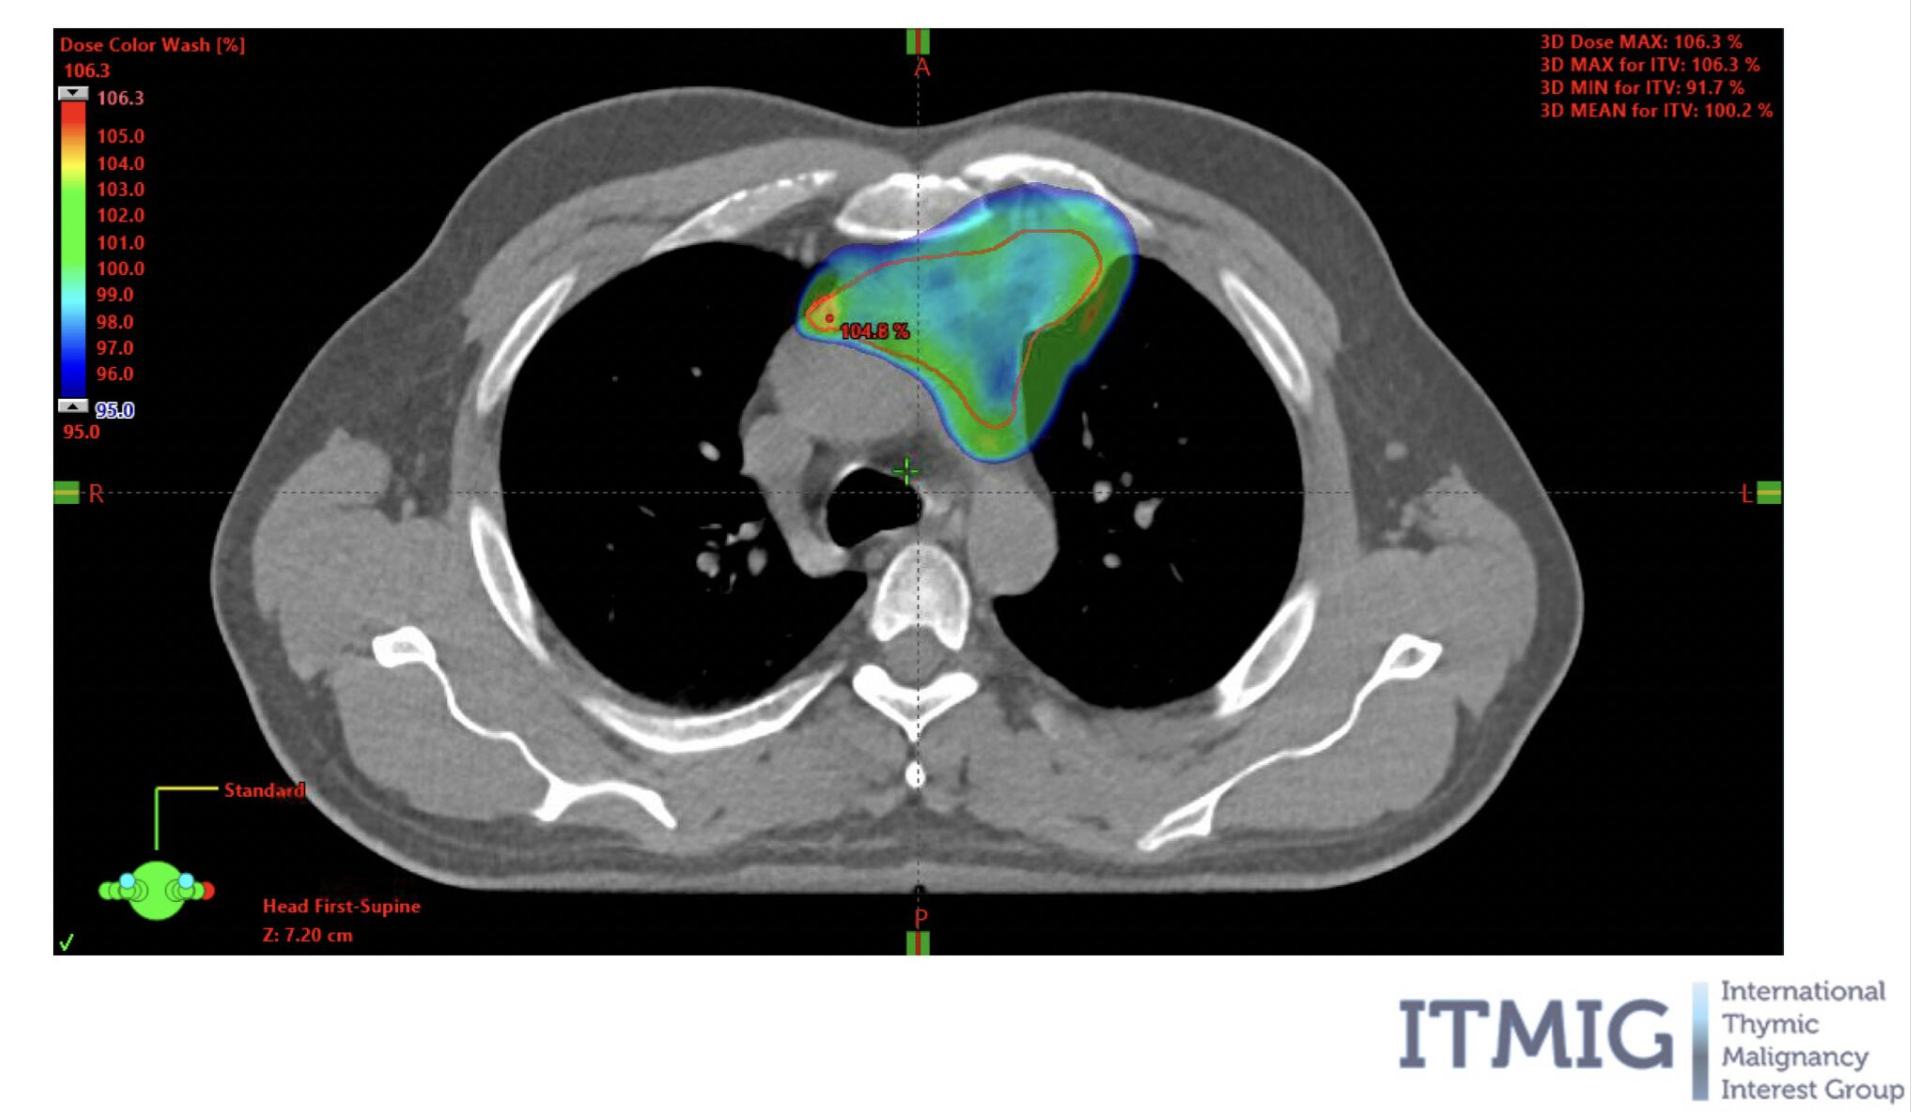

Dr James Wilson is a London-based private oncologist with expertise in lung cancer, skin cancer, and advanced radiotherapy for Stage 4 cancers. He offers rapid access to chemotherapy, immunotherapy, targeted therapy, and precision radiotherapy - including proton beam therapy. Known for clear communication and personalised care, Dr Wilson helps patients take control with expert second opinions and tailored treatment plans. Appointments are often available within days, either in person or via video. Video consultations are often possible on the same or next day. Trusted by patients Specialist in complex and advanced cases Precision-led, consultant-delivered care